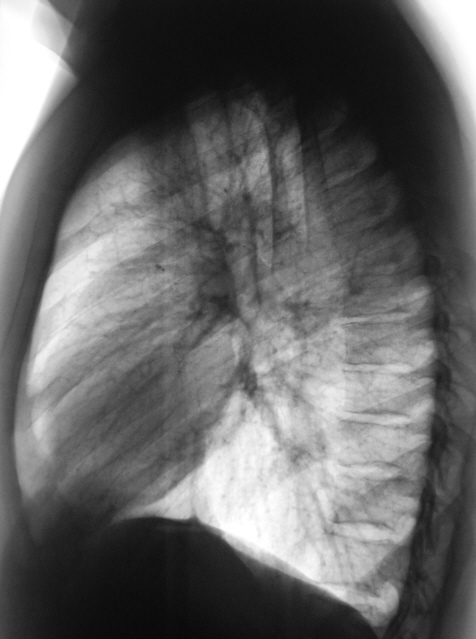

100.Rasshifrovka..jpg

Образование верхней доли левого легкого с дорожкой к корню, мне кажется может оказаться как периферическим раком ,так и туберкуломой.Надо начать с линейной томограммы. А нет ли вздутия переднего отрезка 3 ребра?

Этот дефект на всех снимках - это наше "факсимиле" - шутка. Дефект на экране, мы с ним уже смирились. Мы тоже подумали о периферическим раке и "дорожку" приняли к сведению. По поводу туберкулёза, как - то не подумали. Конечно, и о доброкачественной опухоли также вспомнили. Конечно, все "большие симпатии" в векторе периферического рака лёгкого.

И все таки похоже на туберкулому, мне кажется за год несколько уплотнилось образование, были более четкие,ровные контуры, а сейчас какбы чуть-чуть сжалось(или выдаю желаемое за действительное?). Просто у меня был очень похожий случай,только в нижней доле левого легкого за тенью сердца, с дорожкой к корню с лучистыми (как мне казалось)контурами образование чуть больше вашего,была уверена , что периферический рак, а больной сйчас в туб.диспансере лечит туберкулому.